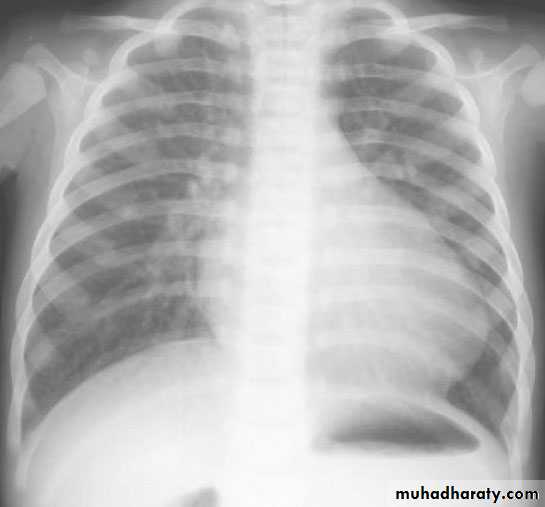

• CXR :

• Egg on side

• Narrow mediastinum